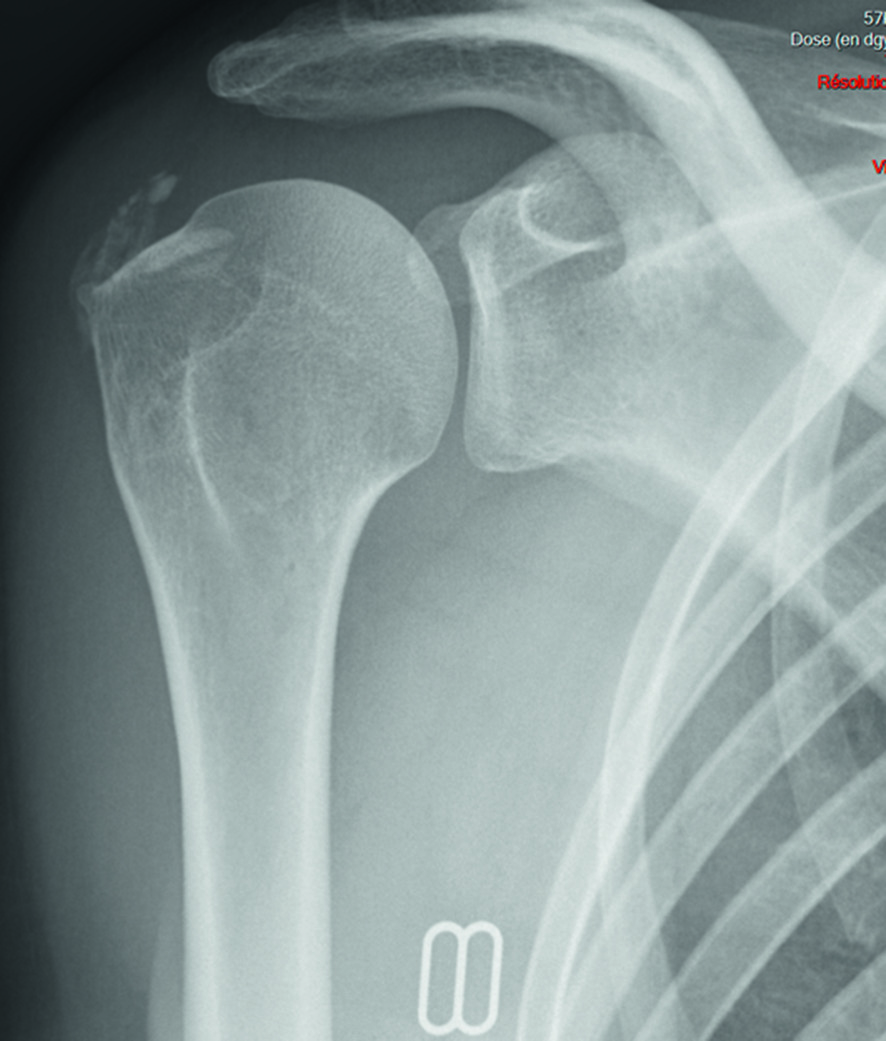

On note des signes radiographiques d’arthrose associant pincement articulaire, condensation, ostéophytose qui peuvent cependant être tardifs (fig. 30.6) (cf. aussi item 129 au chapitre 8).

Fig. 30.6. :

Aspect d’omarthrose excentrée associant pincement articulaire localisé, condensation, ostéophytose de la partie inférieure de la tête humérale, disparition de l’espace sous-acromial.

L’omarthrose primitive dite centrée dans le plan frontal est plus rare et correspond à une véritable atteinte arthrosique de l’articulation glénohumérale avec pincement de l’interligne, condensation sous-chondrale et ostéophytose le plus souvent polaire inférieure avec notamment ostéophyte huméral inférieur en « barbichette » ; elle peut être primitive ou survenir après des lésions cartilagineuses glénohumérales secondaires à une atteinte inflammatoire (polyarthrite rhumatoïde), infectieuse (arthrite septique) ou microcristalline (chondrocalcinose).